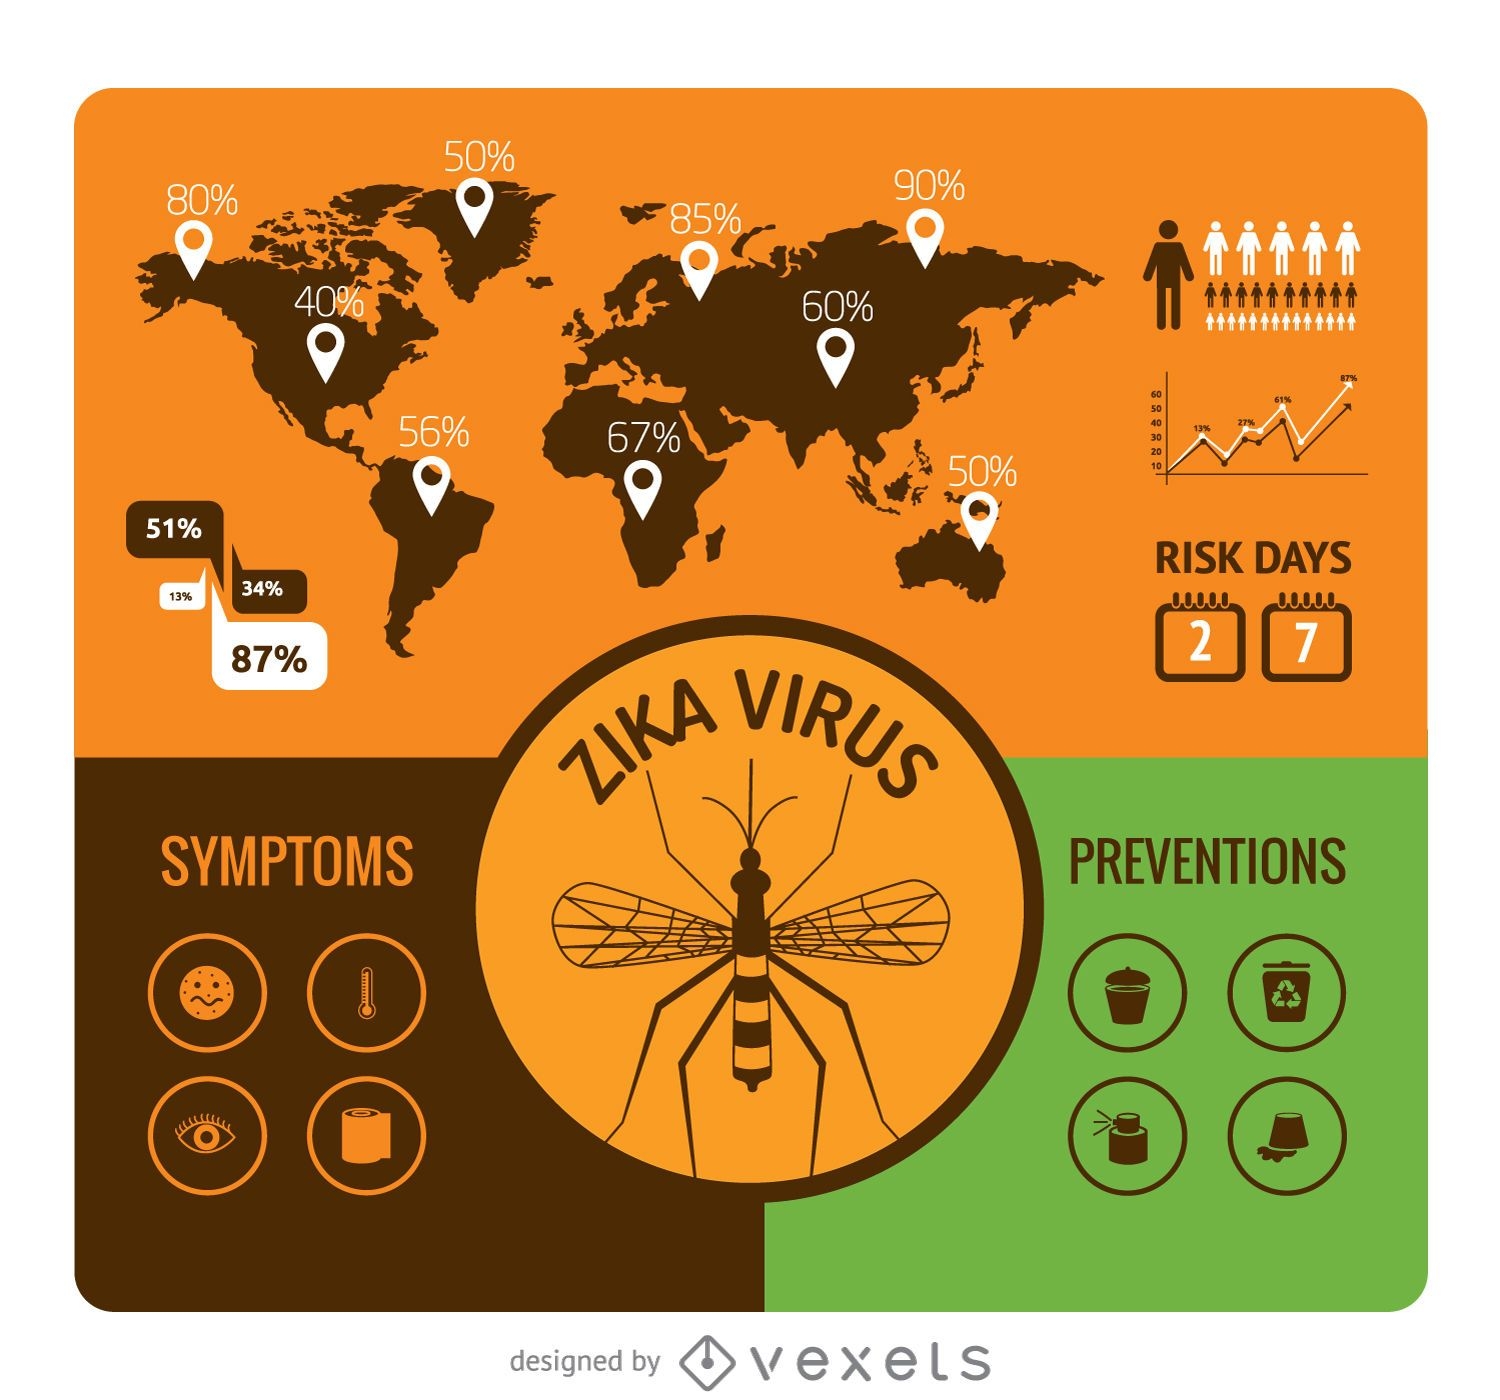

Flat design Zika virus infographic